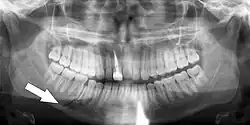

Absence of periodontal ligament space from part or entirety of the root

Cemento-enamel junction appears more apically for the traumatised tooth |